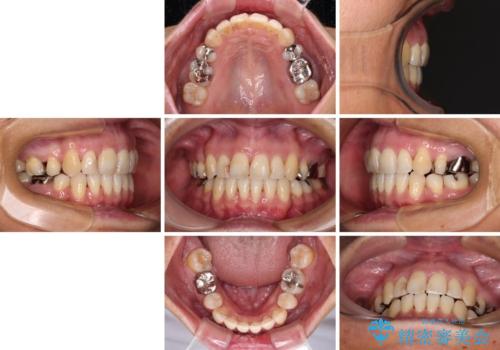

八重歯で口元が膨れている ワイヤー装置での抜歯矯正

- 八重歯と、それによる口元の膨らみを気にして来院された患者様です。

八重歯・デコボコの解消とともに、前方に張り出した上顎前歯を引っ込めることを目的とし、上下左右の第一小臼歯4歯を抜歯をしてワイヤー矯正により治療することとしました。

半年もしないうちに八重歯は解消し、治療も当初予定通り2年強で終えることができました。